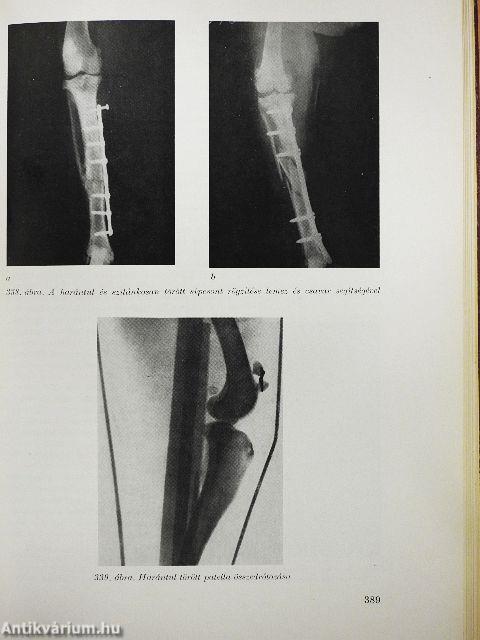

| A végtagcsontok betegségei | 366 |